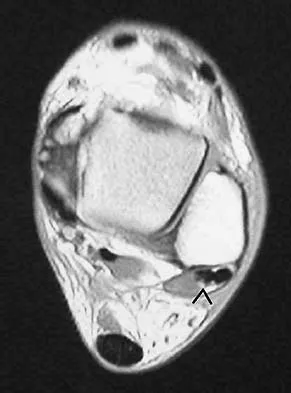

Figure 48 shows an MRI scan of the knee. The arrow is pointing to what structure?

Explanation